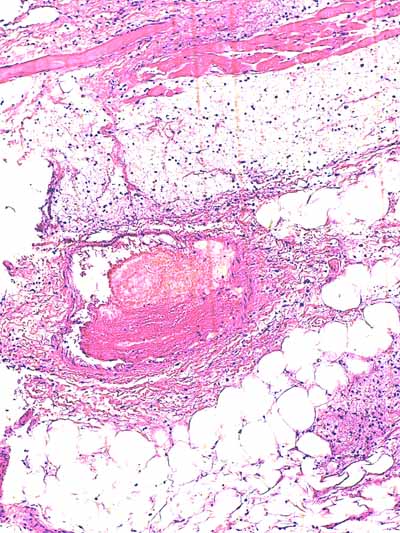

Photo 7 (Hémalun-Eosine X40) : l’hypoderme et le muscle peaucier sont dilacérés

par l’œdème et un infiltrat cellulaire diffus. Un vaisseau sanguin de moyen calibre contient un thrombus fibrineux.

Légendes de la Photo 7 :

- Flèches turquoises : muscle peaucier

- Flèches juanes : œdème et infiltrat neutrophilique dilacérant l’hypoderme et le muscle peaucier

- Ovale turquoise : la lumière d’une veine de moyen calibre est obstruée d’un thrombus fibrineux

- Double flèche verte : épaisseur dermique

- Double flèche bleue : épaisseur hypodermique

- Étoiles bleues : follicules pileux